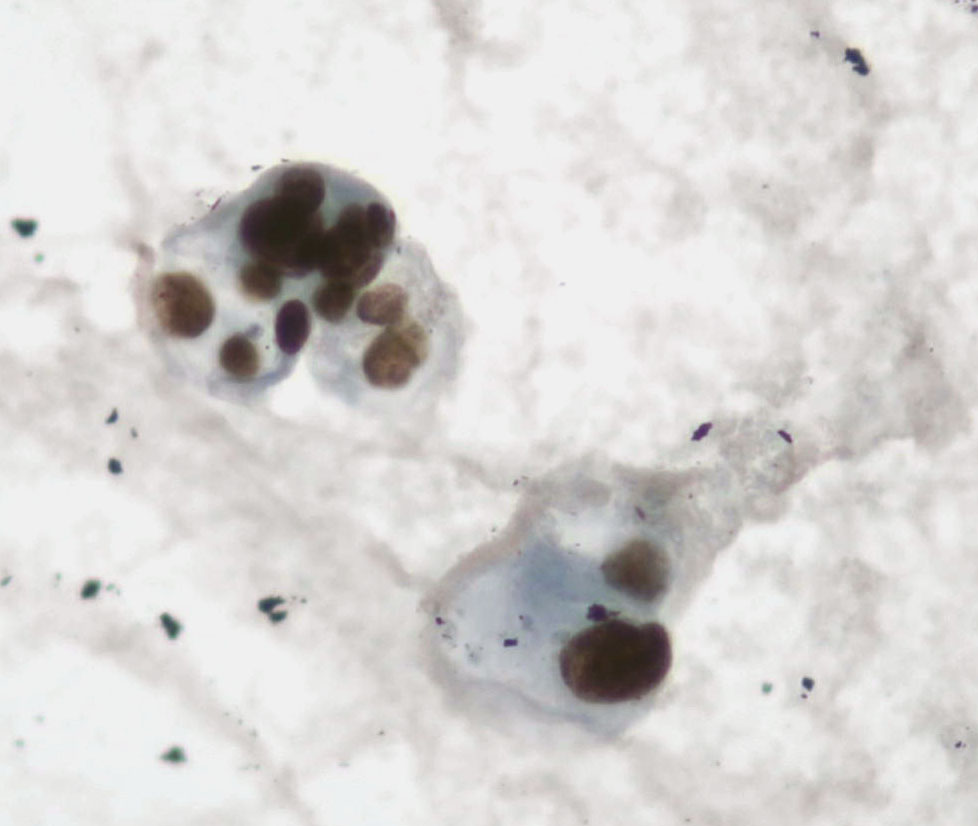

"Two-in-one": lung AC in a pleural effusion: the same cells stained with papanicolaou and then with TTF1. "Cytopathology, doing more with less...."🔬✌️🎯💯🔝 Sociedad Española de Citología SEAP-IAP Cytopathology.org International Academy Cytology